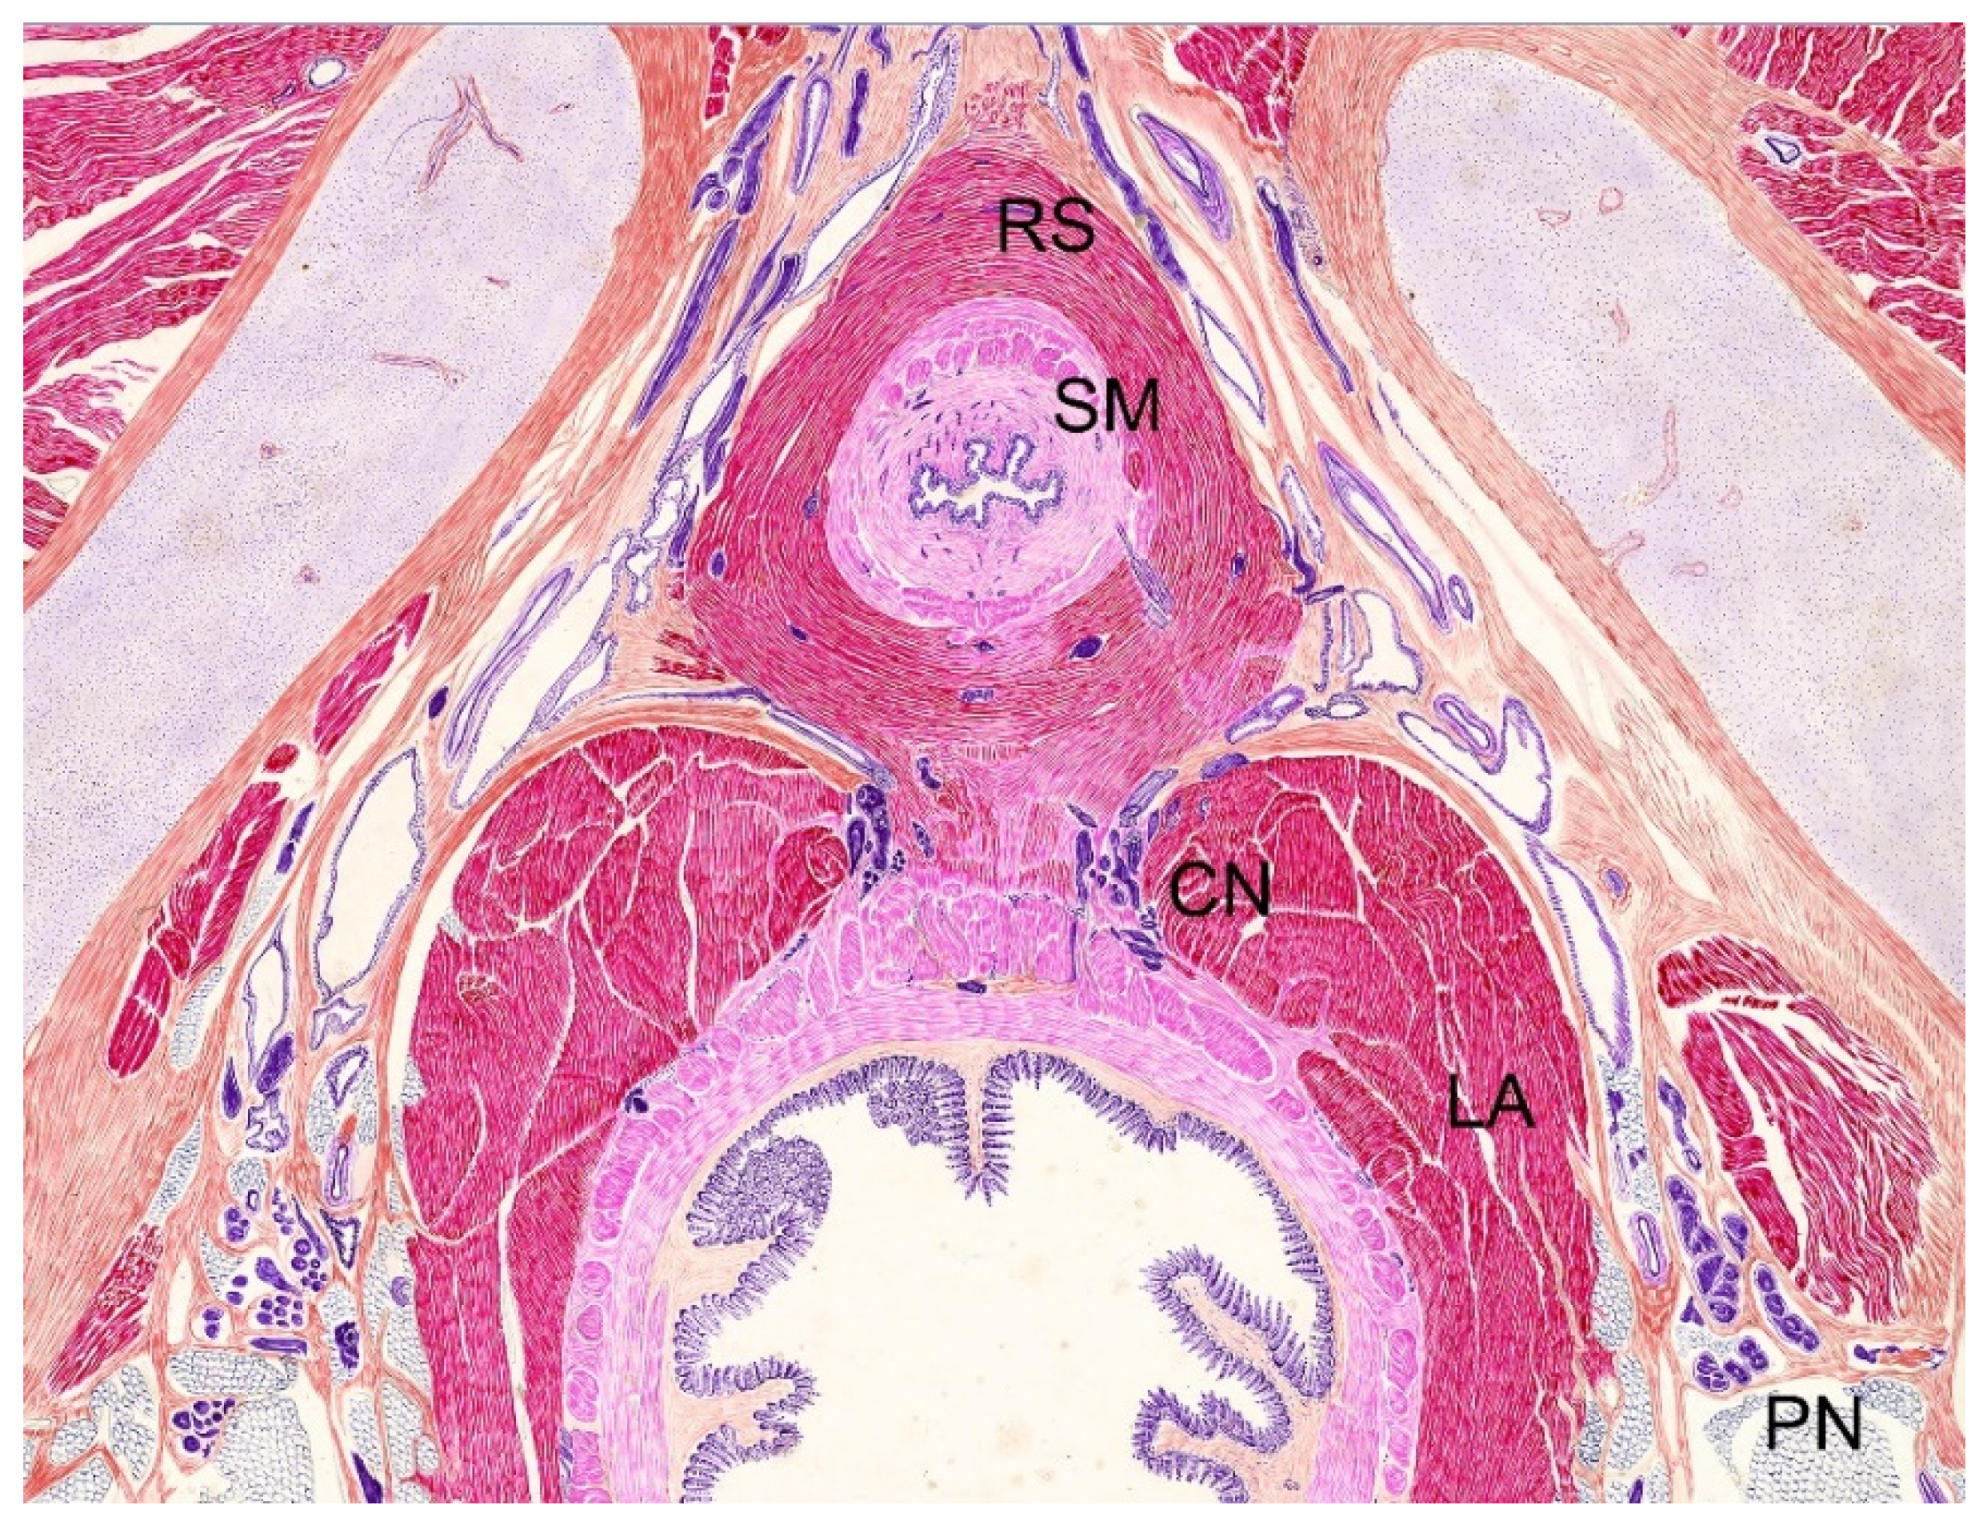

2.1. Surgical Technique

- Gomez, R.G.; Scarberry, K. Anatomy and techniques in posterior urethroplasty. Transl. Androl. Urol. 2018, 7, 567–579. [Google Scholar] [CrossRef]

- Dalpiaz, O.; Mitterberger, M.; Kerschbaumer, A.; Pinggera, G.-M.; Bartsch, G.; Strasser, H. Anatomical approach for surgery of the male posterior urethra. BJU Int. 2008, 102, 1448–1451. [Google Scholar] [CrossRef]